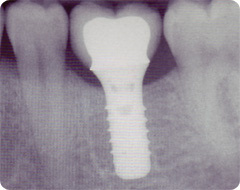

Nur auf dem Röntgenbild (siehe oben) ist zu erkennen,

was sich unter diesem Zahn verbirgt: ein Implantat